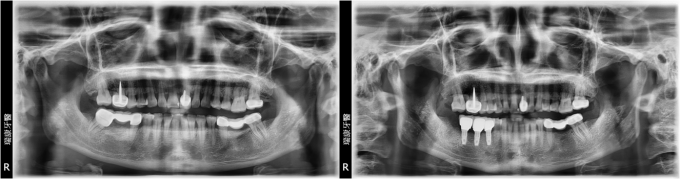

下顎多顆缺牙重建

病患王先生,57年次,上班族

主訴 : 想要重建右下缺牙區

治療計劃 : 安排精密3D電腦斷層評估後,進行人工植牙, 三個月後接出假牙基座印模製作正式假牙!

實例照片僅為資訊介紹及分享,效果可能因個人體質及保養方式不同而有所差異。